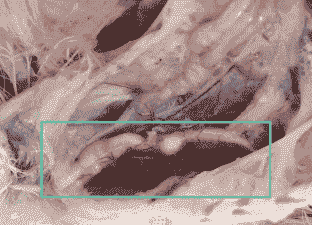

剖检可见液化的卵黄组织,卵巢充血肿大,卵泡出血破裂,生殖道水肿、硬化、萎缩。

剖检可见肾肿大、苍白、输尿管和肾小管尿酸盐沉积。